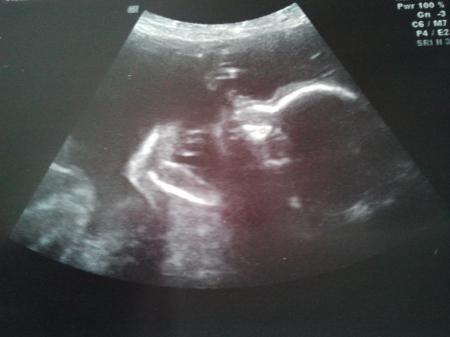

Also die Plazenta liegt direkt über dem MM und somit hab ich absolutes Verbot irgendwas zu machen. Das Positive daran ist, das der GMH noch lang genug ist. Ich darf weiterhin keine Wehen kriegen (haha, weil man das auch so toll beeinflussen kann) und soll mich schonen. Haushaltshilfe wird natürlich weiterhin bewilligt. Wenn der Befund so bleibt läuft definitiv alles auf einen Kaiserschnitt hinaus. Oh man und nun hab ich schon seit Wochen nicht mehr geherzelt. Anfangs fiel es mir nicht schwer, aber nun wird es echt anstrengend. Weiterhin nicht baden, nicht zu heiß duschen und bei dem kleinsten Tropfen Blut wieder ins Krankenhaus. Dafür hab ich noch ein tolles Bild bekommen, was ich euch nicht vorenthalten möchte =) Das ist diesmal wirklich niedlich.

Bild zu